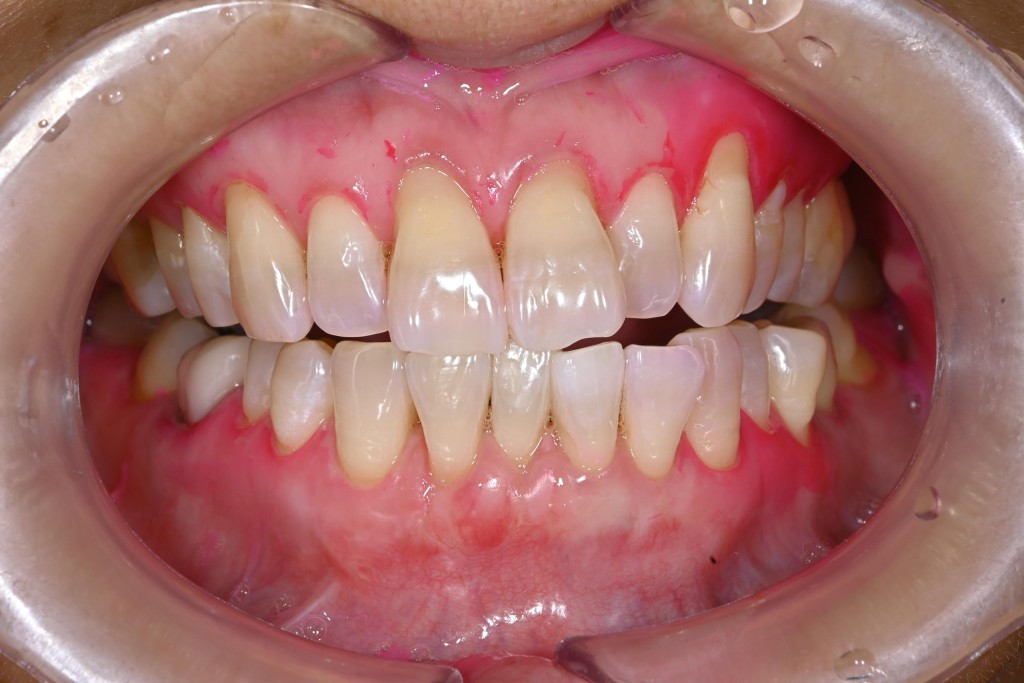

さて今回は下顎の歯肉退縮の症例を紹介します。

| 治療内容 | 歯肉退縮治療(VISTA) |

| 治療期間 | 3ヶ月 |

| 治療費用 | 17万円( 税抜 ) |

| 副作用・リスク | 外科処置が伴うため、術後の疼痛・腫脹・出血・咬合痛などを生じる事があります。 麻酔を行う場合、腫れやむくみを生じる事があります。 |